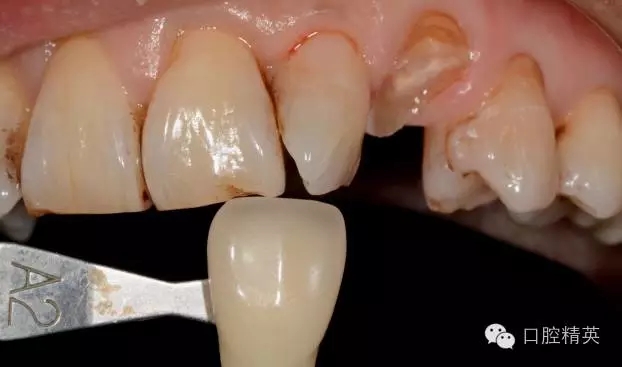

圖4 修復(fù)前選色: